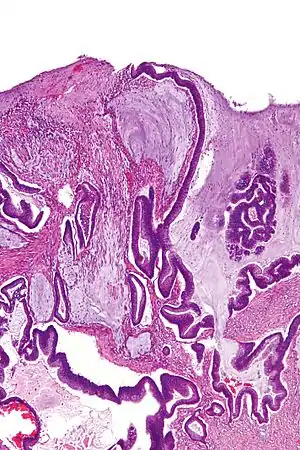

| Micrograph of a mucinous adenocarcinoma of the colon. H&E stain. | |